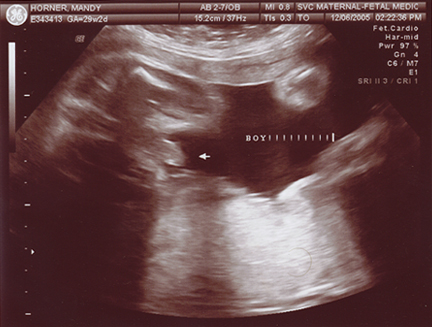

December 10, 2005 - Mandy has gone in for her doctor's appointments, and Evan is doing very well! He is a little over 2 pounds, and he is at 29 to 30 weeks! He is a very active little fellow, Manders can definately tell you that! We plan to go to Sioux Falls at least twice a week when Mandy is at 32 wks. She will undergo NoStress tests. Mandy has a lot better details for you than I would! She always keeps up with Evan on her LiveJournal site!

•  We are still expecting a February 10 or 11 for the DOC.